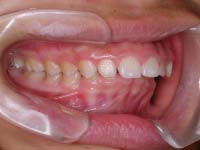

上顎前突症例(じょうがくぜんとつしょうれい) |

| maxillary protrusion(マキシラリープロトゥルージョン) |

上の歯や顎が出た状態です。出っ歯 と言われることもあります。上の歯が飛び出て見えることからその様に呼ばれることも多いですが、場合によっては出っ歯に見えないけど上顎前突 ということもあります。正常の噛み合わせは上の前歯が下の歯より前後的にも垂直的にも3mmほど被さっている状態です。もし下の前歯が上の歯と噛み合わず歯茎と噛む位置にいれば、上顎前突と言えるでしょう。また奥歯、犬歯(糸切り歯)の噛み合わせを見たとき、上の歯の奥歯の方が下の歯の奥歯より少し後ろにいるのが正常です。するとキレイに並んだ歯はギザギザがピッタリ合うように噛み合います。おそらく前歯の噛み合わせにズレが有る人は、上下のガタガタの量が同じであれば、前歯だけでなく奥歯の噛み合わせもズレが有るでしょう。